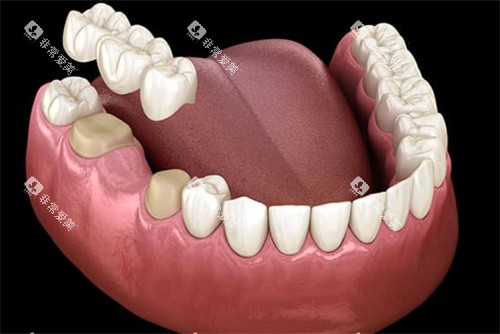

牙槽骨萎缩的危害不容小觑。它会重度影响牙齿修复结果,对于传统假牙修复,萎缩的牙槽骨无法提供足够的支持和固位,导致假牙容易松动、移位,影响咀嚼功能和舒适度。在种植牙修复中,牙槽骨的骨量不足可能使种植体无法获得良好的初期稳定性,增加种植失败风险。

研究显示,种植牙修复后,骨量流失速度可降低60%以上,长久保持牙槽骨形态,维持面部自然轮廓。相比之下,活动假牙因仅依靠牙床黏膜和邻牙支撑,无法提供足够的生理性刺激,不能有效防止牙槽骨吸收。